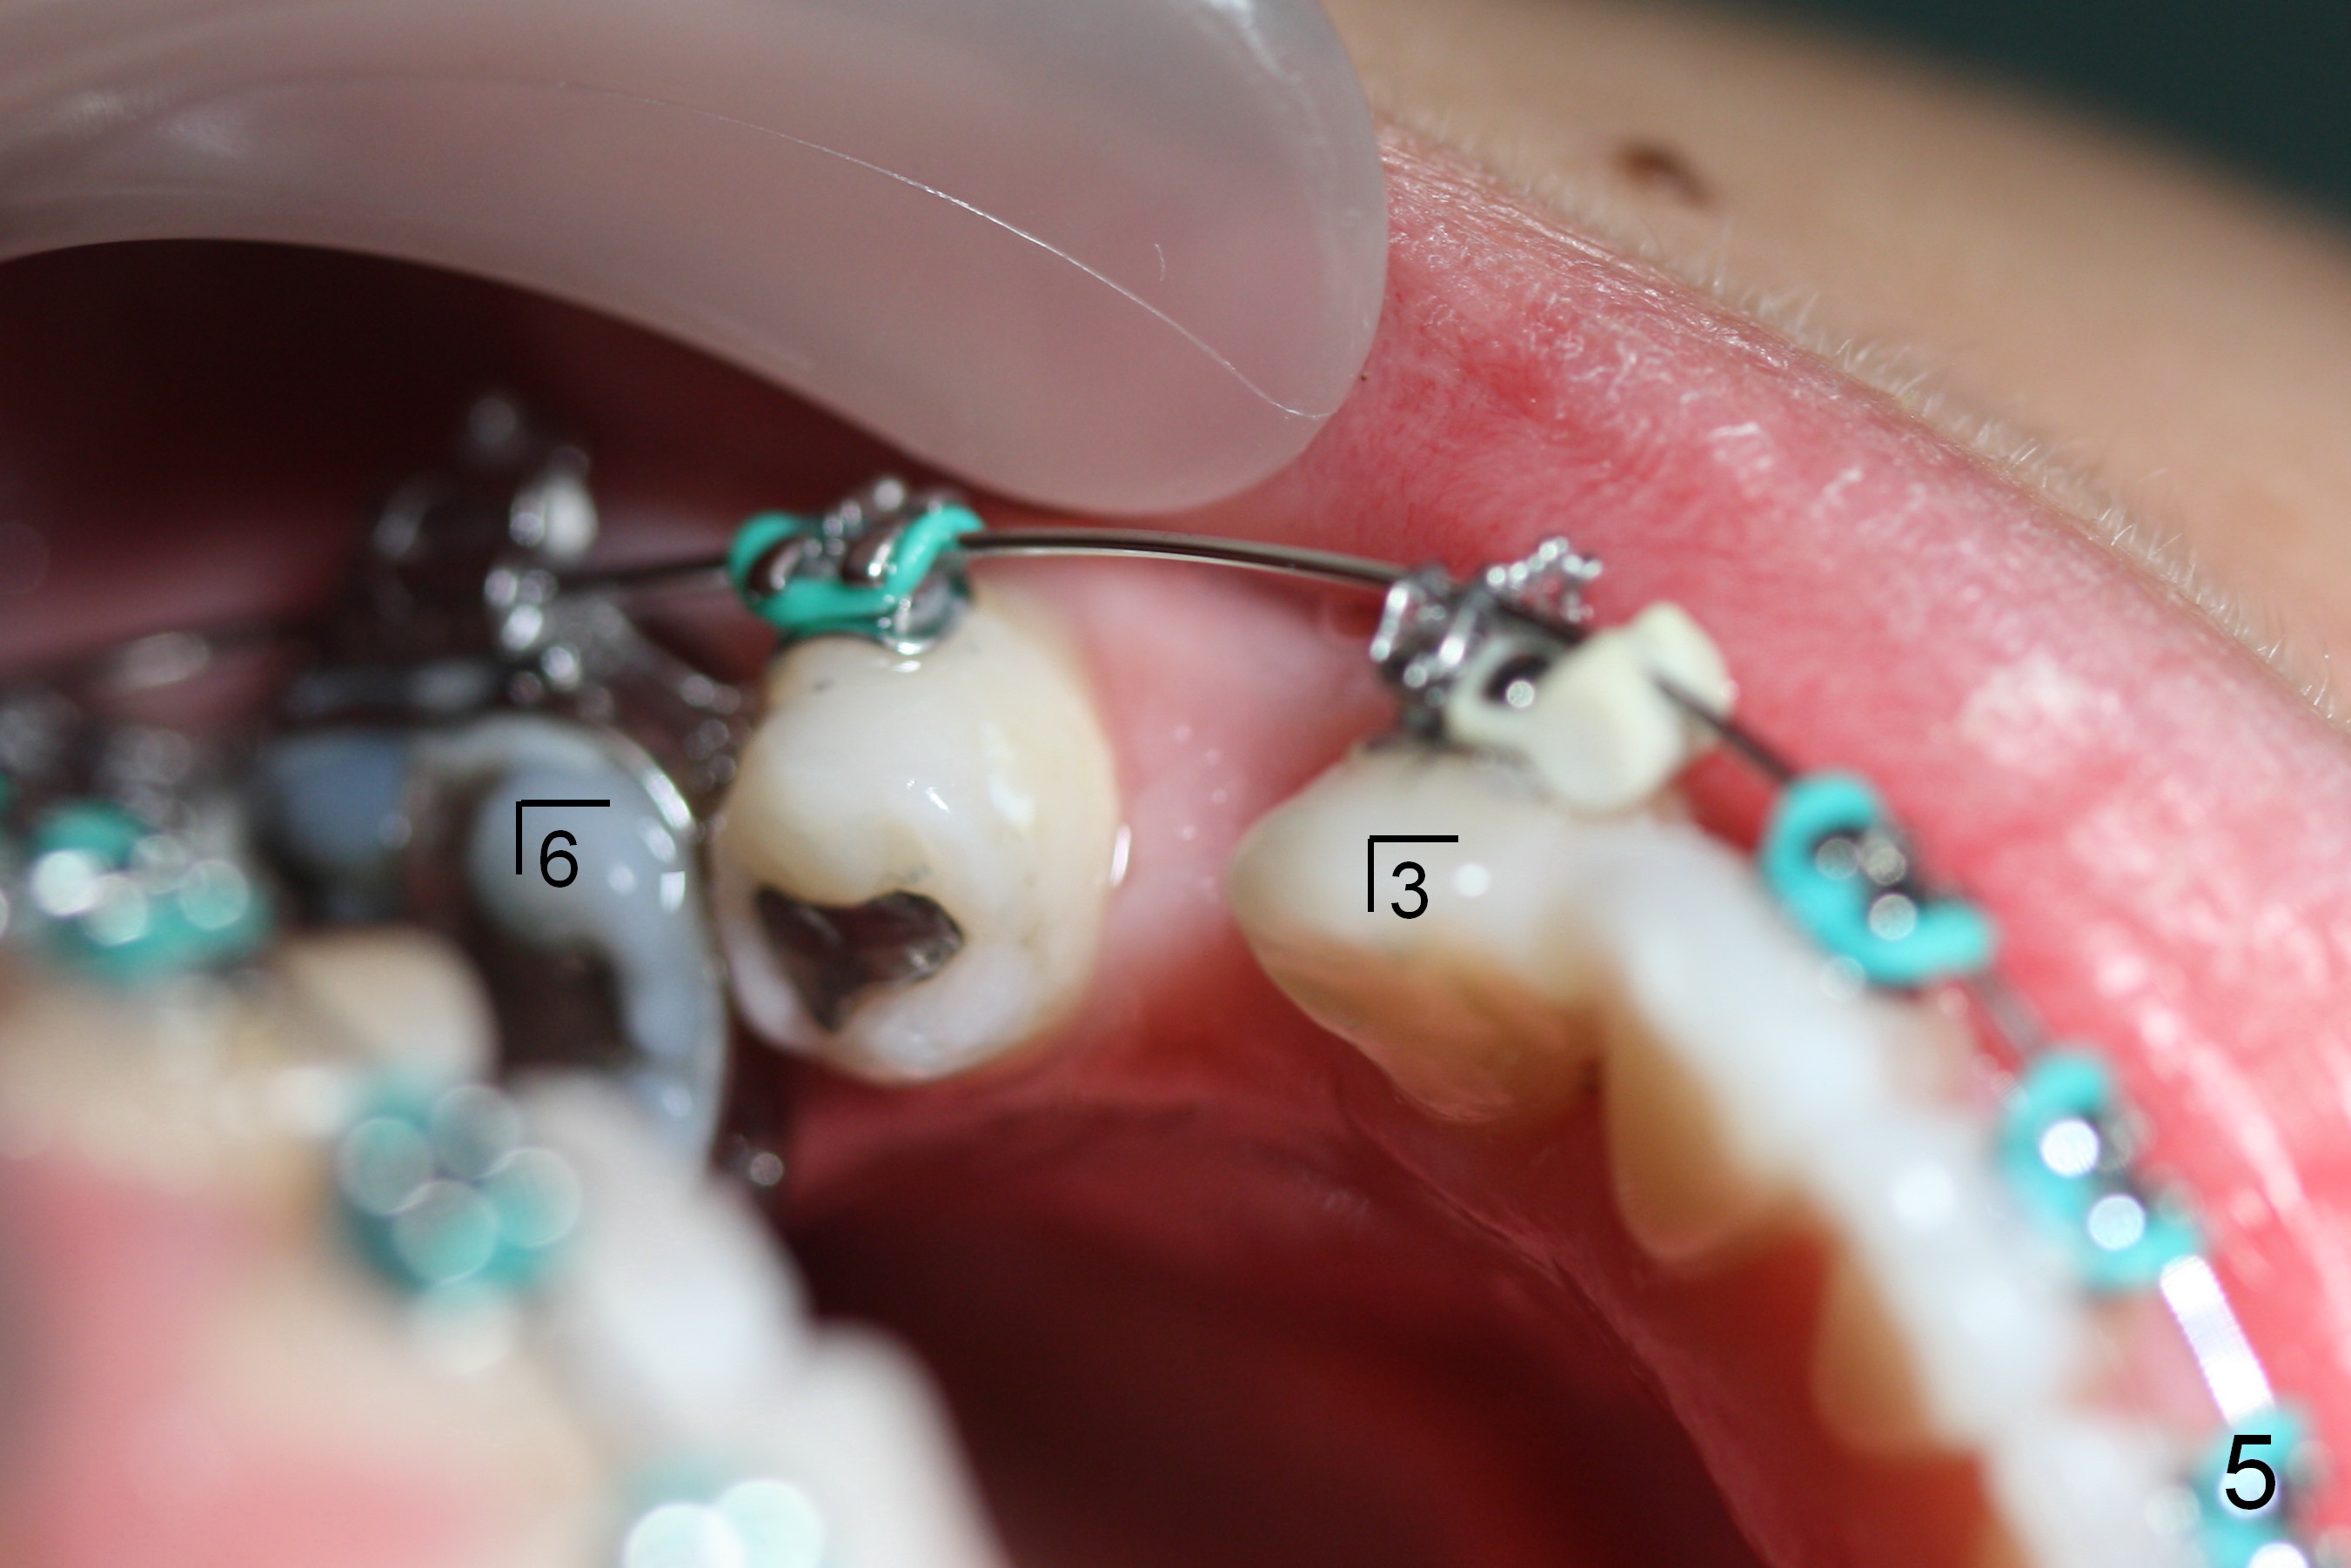

The lower 4s are expected to be extracted. On the day of surgery, LR 5 is found to have been heavily restored (MO amalgam, DO composite, Fig.1); the prognosis is less favorable than LR 4. So the former is extracted (Fig.2).

On the other side, the canine area is crowded (Fig.1: 3). Therefore the lower left 1st bicuspid is extracted (Fig.2). Fig.2 is taken on the day of banding (2 weeks post extraction). A Niti wire (.014") is used. According to model surgery, the anterior teeth are to be distalized (Fig.2 arrows).